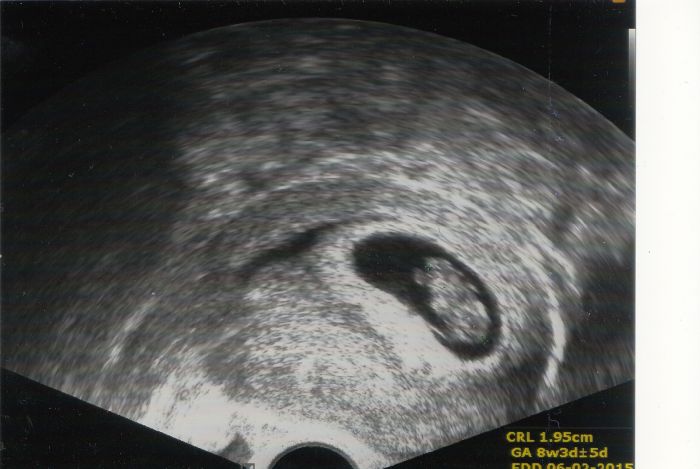

Ahoja holky, tak kontrola za mnou (ufff) a vše v pořádku. Pouze mi v krvi zjistili nějakou protilátku (nespecifickou), kterou časem bude Dr. sledovat. Jinak prcek má CRL (od zadečku k hlavě) 2 cm (dle dnešního UTZ to odpovídá 8+3, dle původního 9+0). Jinak na screening musím jinam - také do jiného města.. a vlastně 2x - jednou na krev, podruhé na UTZ. Je to docela otravné, ale tak co už. Přikládám první foto (Dr za něj chtěla 100 Kč - nevím podle čeho určují ty ceny :o))).. No nechala jsem si ho udělat pro taťuldu, aby konečně viděl, že snad budeme brzy 3 :o)